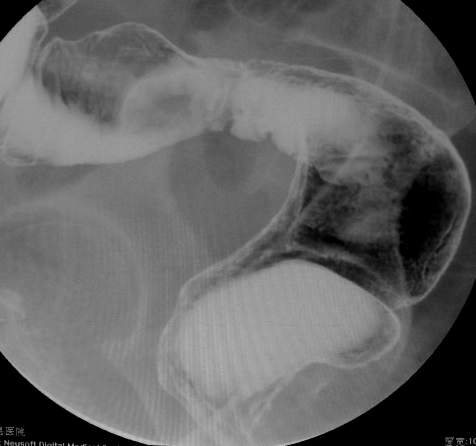

67岁女性,腹痛、腹胀半月余。查:右侧腹部有触痛,可触及肿物。

大家可以和x6045比较一下。x6045病理结果为粘液癌。

常规考虑---结肠癌,不排除诱发肠套叠了。

谢谢大家讨论。与x6045完全不同。本例手术结果为右侧结肠旁沟及盆腔多发脓肿。术后病人恢复良好,现已出院。

感谢楼主反馈结果!造影见果核征,首先考虑肿瘤,即使误诊也应该这样考虑。